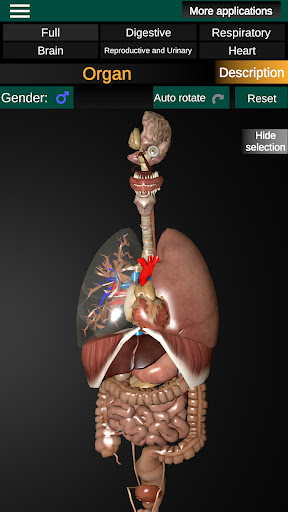

Internal Organs in 3D Anatomy لـ Vodafone Smart N9 Lite

(الأجهزة الداخلية في)

Internal Organs 3D Anatomy 3.4

يمكنك هنا تنزيل ملف حزمة تطبيق أندرويد "Internal Organs 3D Anatomy" الخاصة بجهازVodafone Smart N9 Lite مجانًا، نسخة ملف حزمة تطبيق أندرويد - 3.4 للتحميل على Vodafone Smart N9 Lite اضغط ببساطة على هذا الزر. إنه سهل وآمن. نحن نقدم فقط ملفات حزمة تطبيق أندرويد الأصلية. إذا انتهكت أية مواد موجودة في الموقع حقوقك قم بإبلاغنا من خلال